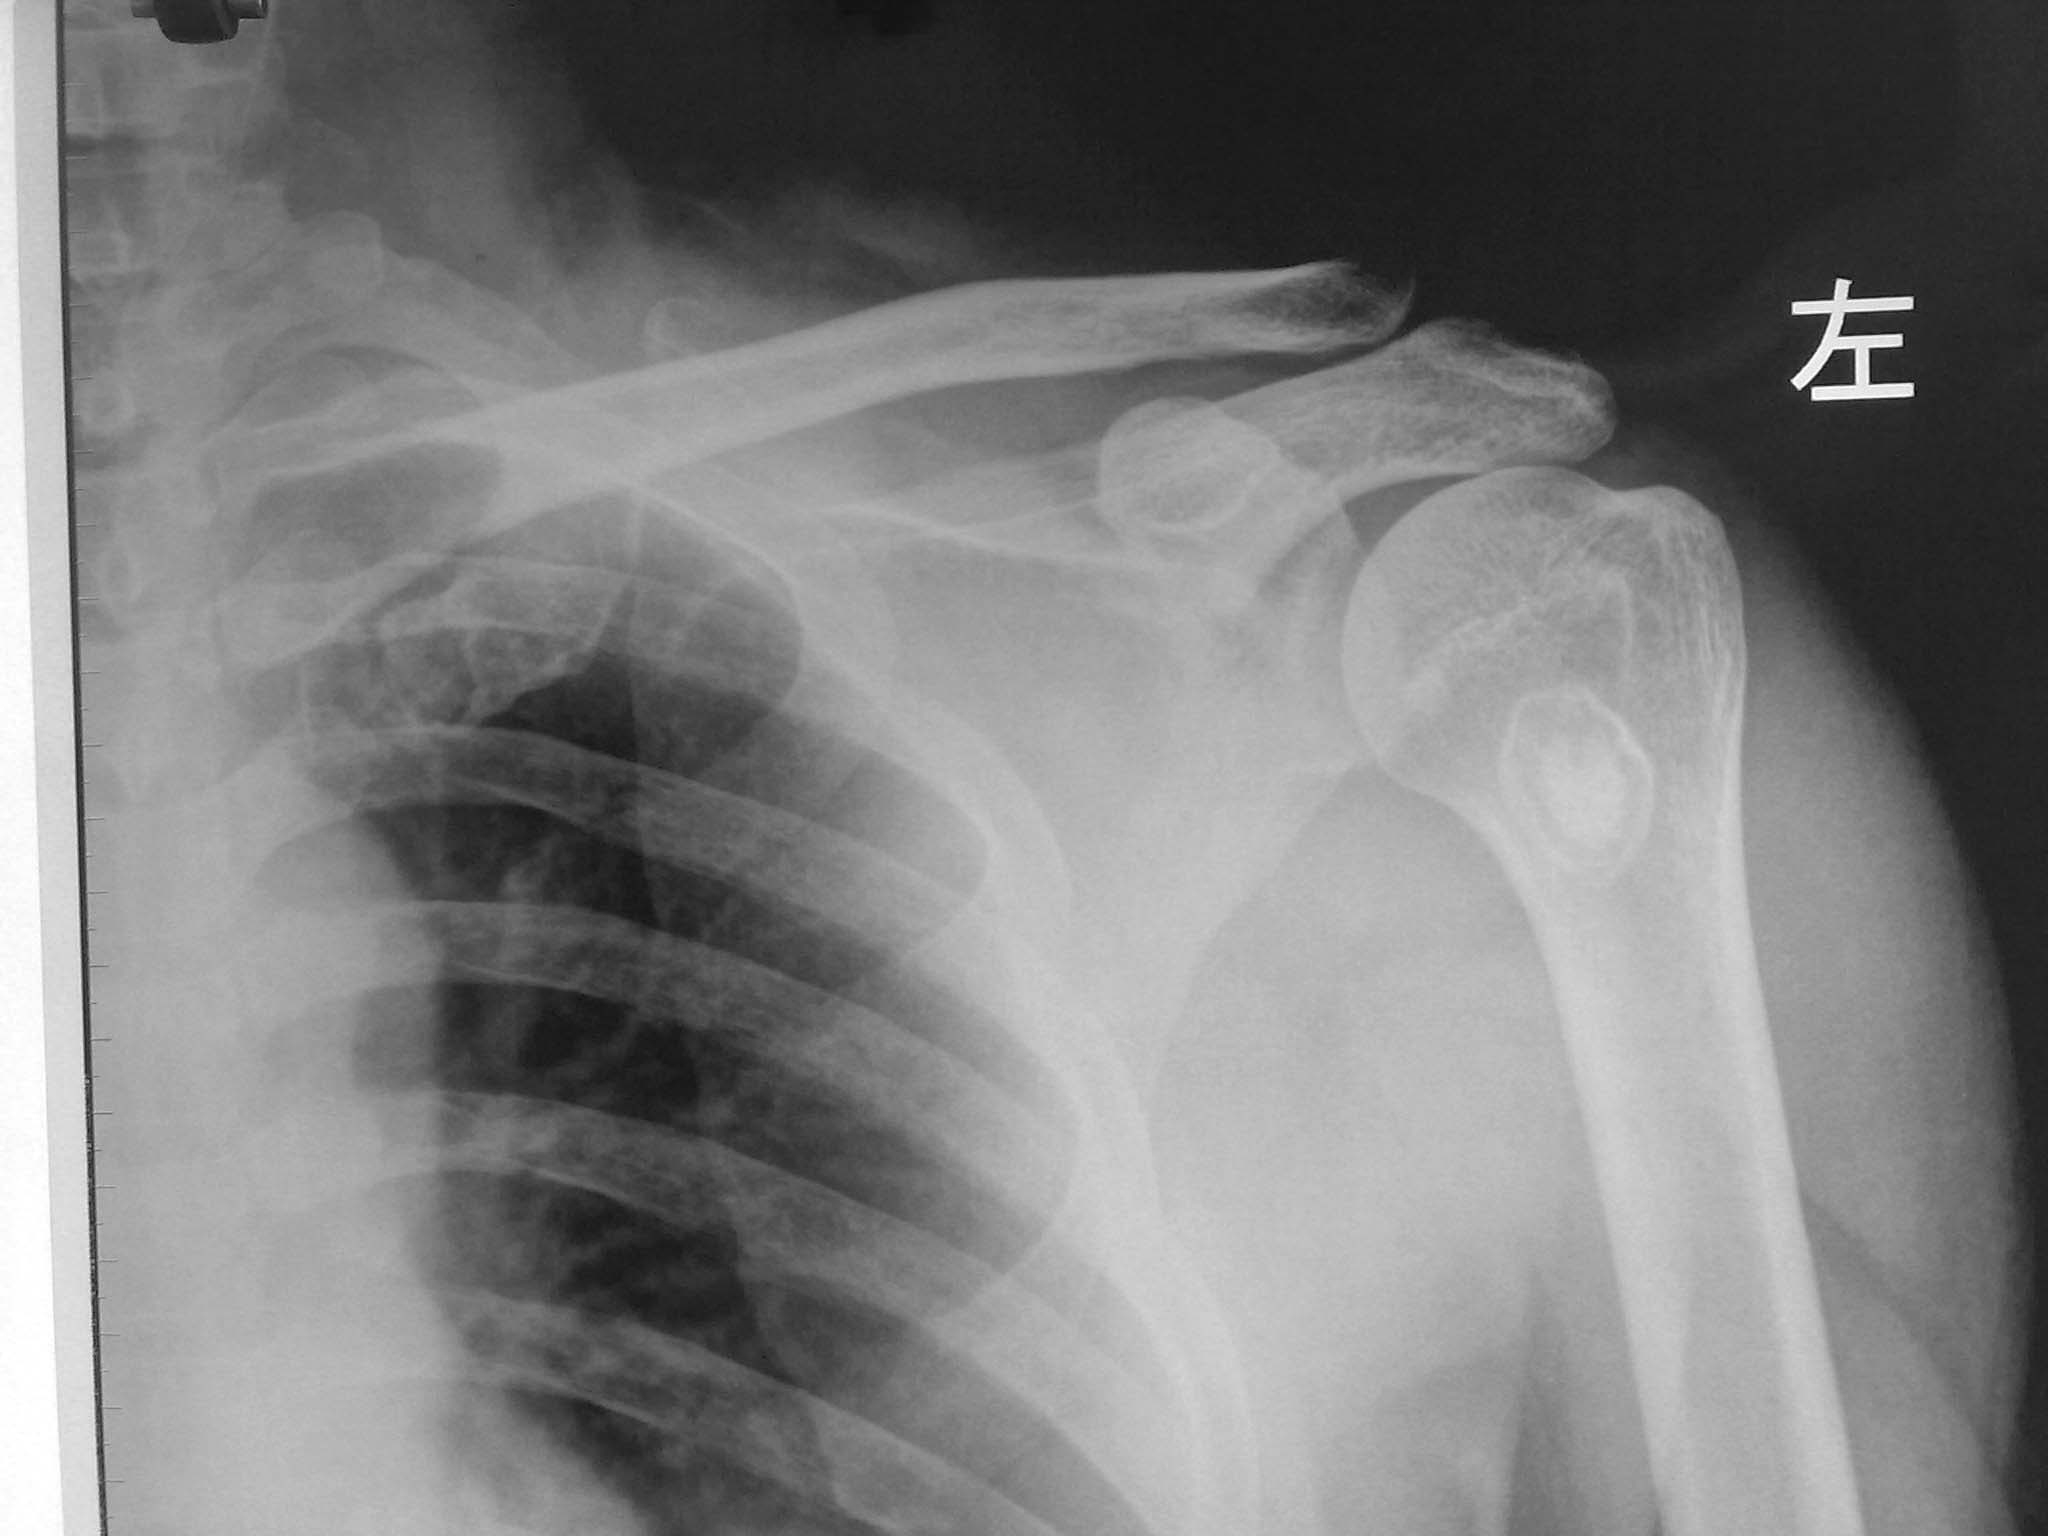

标题: X7640:左肩疼痛。

男性,51岁,左肩疼痛一年,活动不受限。

肱骨上端类圆形低密度影,边缘硬化,其中可见圆形高密度影。我考虑骨化性纤维瘤可能性大,不除外局限性硬化性骨纤

左肱骨上端髓腔内可见环状低密度影,周边硬化,内见圆形高密度影,肱骨皮质及软组织未见异常,支持考虑内生性软骨瘤可能性大,骨梗死??